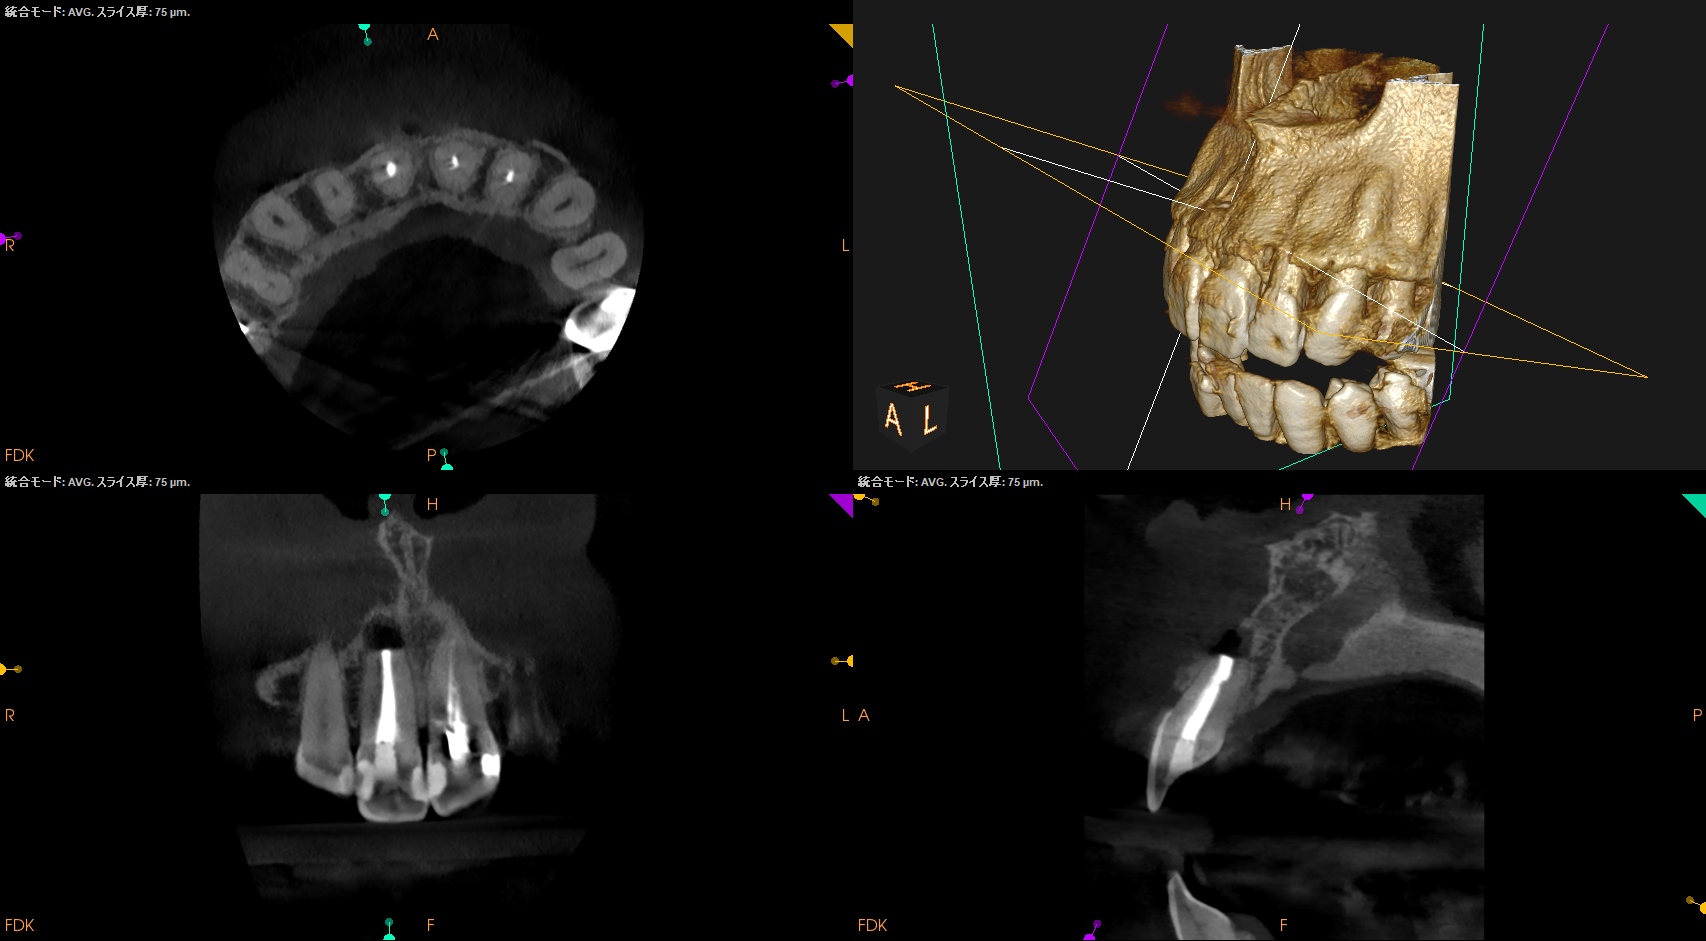

CBCT(2025.6.3)

#8はApexが歯槽骨からはみ出ている。

PA所見から考察するに、再治療よりも外科治療だろう。

PA, CBCTを撮影した。

初診時と比較した。

劇的に状況は改善している。

#8,9,10に最終補綴もOKだろう。